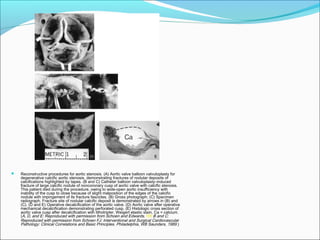

 Reconstructive procedures for aortic stenosis. (A) Aortic valve balloon valvuloplasty for

degenerative calcific aortic stenosis, demonstrating fractures of nodular deposits of

calcifications highlighted by tapes. (B and C) Catheter balloon valvuloplasty–induced

fracture of large calcific nodule of noncoronary cusp of aortic valve with calcific stenosis.

This patient died during the procedure, owing to wide-open aortic insufficiency with

inability of the cusp to close because of slight malposition of the edges of the calcific

nodule with impingement of its fracture fascicles. (B) Gross photograph; (C) Specimen

radiograph. Fracture site of nodular calcific deposit is demonstrated by arrows in (B) and

(C). (D and E) Operative decalcification of the aortic valve. (D) Aortic valve after operative

mechanical decalcification demonstrating perforated cusp. (E) Histologic cross section of

aortic valve cusp after decalcification with lithotripter. Weigert elastic stain. Ca = calcium.

(A, D, and E: Reproduced with permission from Schoen and Edwards.185 B and C:

Reproduced with permission from Schoen FJ: Interventional and Surgical Cardiovascular

Pathology: Clinical Correlations and Basic Principles. Philadelphia, WB Saunders, 1989.)